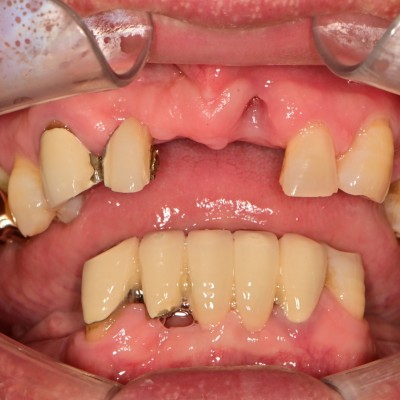

만 50세 전체 임플란트 증례입니다. 전체 임플란트 증례입니다. 18개의 임플란트로 완성하였습니다.

47세 전체임플란트 증례 전체임플란트로 진행하였습니다.